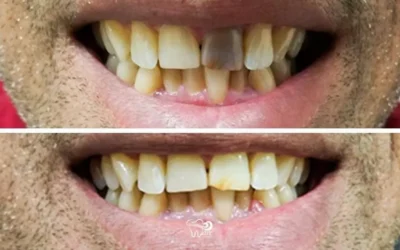

Before/After: Replacing Failing Crowns

Before/After: Replacing Failing Crowns From the photos, it's hard to believe this is even the same...